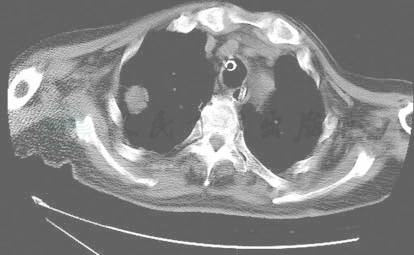

入院后行机械通气,给予哌拉西林/他唑巴坦、多黏菌素E抗感染,解痉化痰,降颅压,营养支持。虽给予广谱抗菌药物治疗但仍发热,体温37.4~38.5℃。分析患者长期应用广谱抗菌药物,口腔存在溃疡、吸痰为血性痰、痰量多,考虑存在真菌感染,故于入院第3日(2007-3-8)给予伏立康唑静滴进行经验性抗真菌治疗,首次给予400mg q12h;翌日开始给予200mg q12h静滴,静点10天后改伏立康唑为200mg q12h鼻饲。应用伏立康唑2天后(2007-3-10)体温开始下降,于3月13日降至正常,气管内痰量明显减少,呼吸困难消失,上消化道出血停止并开始肠内营养。化验:WBC 7.05×109/L,N 80.54%,Hb 80g/L,PLT 167×109/L,BUN 2.89mmol/L,CRE 31μmol/L,K+ 3.9mmol/L,Na+ 142mmol/L,Cl-106mmol/L,ALT 40IU/L,AST 48IU/L,ALB 29.6g/L。3月21日成功撤机后行CT检查,CT报告:右肺上叶尖后段见一不规则团块状阴影,大小约4.7cm×3.2cm,CT值10HU,中间见一类圆形空洞影,洞壁光滑。右下肺见大片高密度影,其内见支气管影,邻近胸膜见一丘形软组织密度影,CT值15HU,最厚1.5cm。左肺下叶后基底段见斑片状模糊影(图2)。

图2-1 撤机当日胸部CT示右肺上叶尖后段见一不规则团块状阴影,大小约4.7cm×3.2cm,CT值10HU,中间见一类圆形空洞影,洞壁光滑。右下肺见大片高密度影,其内见支气管影,邻近胸膜见一丘形软组织密度影,CT值15HU,最厚1.5cm。左肺下叶后基底段见斑片状模糊影

图2-2 撤机当日胸部CT示右肺上叶尖后段见一不规则团块状阴影,大小约4.7cm×3.2cm,CT值10HU,中间见一类圆形空洞影,洞壁光滑。右下肺见大片高密度影,其内见支气管影,邻近胸膜见一丘形软组织密度影,CT值15HU,最厚1.5cm。左肺下叶后基底段见斑片状模糊影

图2-3 撤机当日胸部CT示右肺上叶尖后段见一不规则团块状阴影,大小约4.7cm×3.2cm,CT值10HU,中间见一类圆形空洞影,洞壁光滑。右下肺见大片高密度影,其内见支气管影,邻近胸膜见一丘形软组织密度影,CT值15HU,最厚1.5cm。左肺下叶后基底段见斑片状模糊影

图2-4 撤机当日胸部CT示右肺上叶尖后段见一不规则团块状阴影,大小约4.7cm×3.2cm,CT值10HU,中间见一类圆形空洞影,洞壁光滑。右下肺见大片高密度影,其内见支气管影,邻近胸膜见一丘形软组织密度影,CT值15HU,最厚1.5cm。左肺下叶后基底段见斑片状模糊影

图2-5 撤机当日胸部CT示右肺上叶尖后段见一不规则团块状阴影,大小约4.7cm×3.2cm,CT值10HU,中间见一类圆形空洞影,洞壁光滑。右下肺见大片高密度影,其内见支气管影,邻近胸膜见一丘形软组织密度影,CT值15HU,最厚1.5cm。左肺下叶后基底段见斑片状模糊影

图2-6 撤机当日胸部CT示右肺上叶尖后段见一不规则团块状阴影,大小约4.7cm×3.2cm,CT值10HU,中间见一类圆形空洞影,洞壁光滑。右下肺见大片高密度影,其内见支气管影,邻近胸膜见一丘形软组织密度影,CT值15HU,最厚1.5cm。左肺下叶后基底段见斑片状模糊影